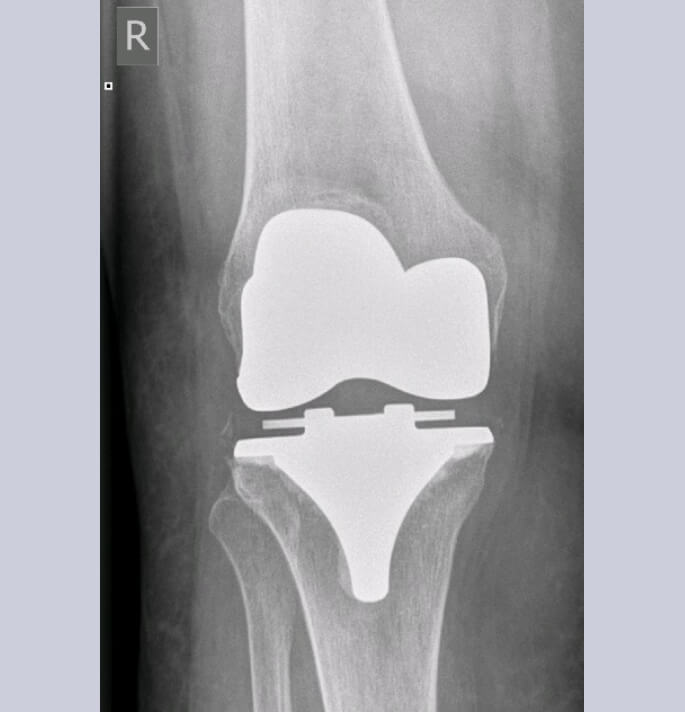

Bij totale artrose van het kniegewricht bestaat de enige oplossing uit een totale knie artroplastie.

Globaal zijn er 2 belangrijke technieken voor het plaatsen van een totale knieartroplastie.

De ” gemeten resectie techniek” (measured resection) waarbij hoofdzakelijk rekening wordt gehouden met de beenderige contouren en assen van het been (ook robots maken hoofdzakelijk

gebruik van deze techniek) of

De “gebalanceerde resectie techniek” (balanced resection) waarbij het plaatsen van de prothese mede begeleid wordt door de correcte spanning van deomliggende weke delen (ligamenten pezen en spieren). Het zijn deze weke delen welke in de postoperatieve fase een goede stabiliteit en mobiliteit zullen bewerkstelligen. Het belang van deze laatste techniek werd bevestigd door de informatie die we verkregen bij het gebruik van de E-lbra balancer welke door ons werd ontwikkeld.

Patiënten voor een knieartroplastie worden opgenomen in het ERAS (ENHANCED RECOVERY AFTER SURGERY) traject. Door intense samenwerking en afstemming van de activiteiten van zowel logistiek, verpleging, kinesitherapie, ergotherapie, anesthesie en chirurgie wordt een geoptimaliseerd herstel beoogd wat ons ook toelaat om in geselecteerde patiënten dergelijke chirurgie via daghospitaal aan te bieden.